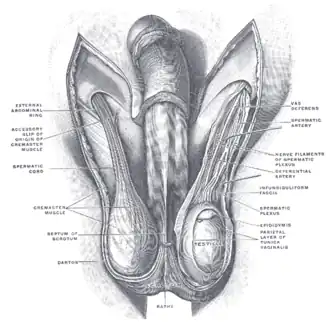

Diagram of the external features and surrounding structures of the testicles of an adult male | |

Blood supply and lymphatic drainage

The testis has three sources of arterial blood supply: the testicular artery, the cremasteric artery, and the artery to the ductus deferens.[12] Blood supply and lymphatic drainage of the testes and scrotum are distinct:

- The paired testicular arteries arise directly from the abdominal aorta and descend through the inguinal canal, while the scrotum and the rest of the external genitalia is supplied by the internal pudendal artery (a branch of the internal iliac artery).[13][14]

- The testis has collateral blood supply from the cremasteric artery (a branch of the inferior epigastric artery, which is a branch of the external iliac artery), and the artery to the ductus deferens (a branch of the inferior vesical artery, which is a branch of the internal iliac artery).[15][16] Therefore, if the testicular artery is ligated, e.g., during a Fowler-Stevens orchiopexy for a high undescended testis, the testis will usually survive on these other blood supplies.[17]

- Lymphatic drainage of the testes follows the testicular arteries back to the paraaortic lymph nodes, while lymph from the scrotum drains to the inguinal lymph nodes.[13][16]

Layers

Many anatomical features of the adult testis reflect its developmental origin in the abdomen. The layers of tissue enclosing each testicle are derived from the layers of the anterior abdominal wall.[1] The cremasteric muscle arises from the internal oblique muscle.[1][18]

The cremasteric muscle covers the testicles and the spermatic cord.[22] When this muscle contracts, the cord shortens and the testicles move closer up toward the body, which provides slightly more warmth to maintain optimal testicular temperature.[22] When cooling is required, the cremasteric muscle relaxes and the testicles lower away from the warm body and are able to cool.[22] Contraction also occurs in response to physical stress, such as blunt trauma; the testicles withdraw and the scrotum shrinks very close to the body in an effort to protect them.[23]